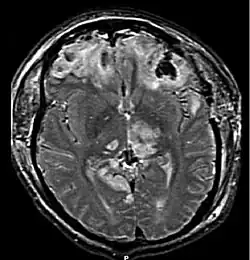

![]() Компьютерная томография, показывающая ушиб головного мозга | |

Ушиб головного мозга (лат. contusio cerebri) — черепно-мозговая травма, при которой происходит поражение непосредственно тканей головного мозга, всегда сопровождается наличием очага некроза нервной ткани. Наиболее часто очаги повреждения располагаются в области лобных, височных и затылочных долей. Повреждения, развившиеся при травме, могут быть как односторонние, так и двухсторонние[2].